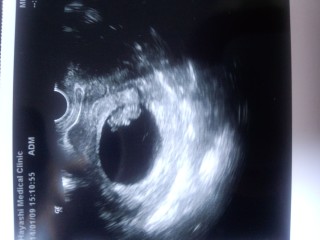

前日に絨毛膜下血腫で 大量出血、即入院。 当日、翌日のエコーで 元気な姿を見せてくれました! 元気に育ってね!

前回の妊娠では心臓がぱくぱく動くところを 見られないまま流産してしまいましたが、 今回は見ることができました! このまま元気に育ってほしいです。